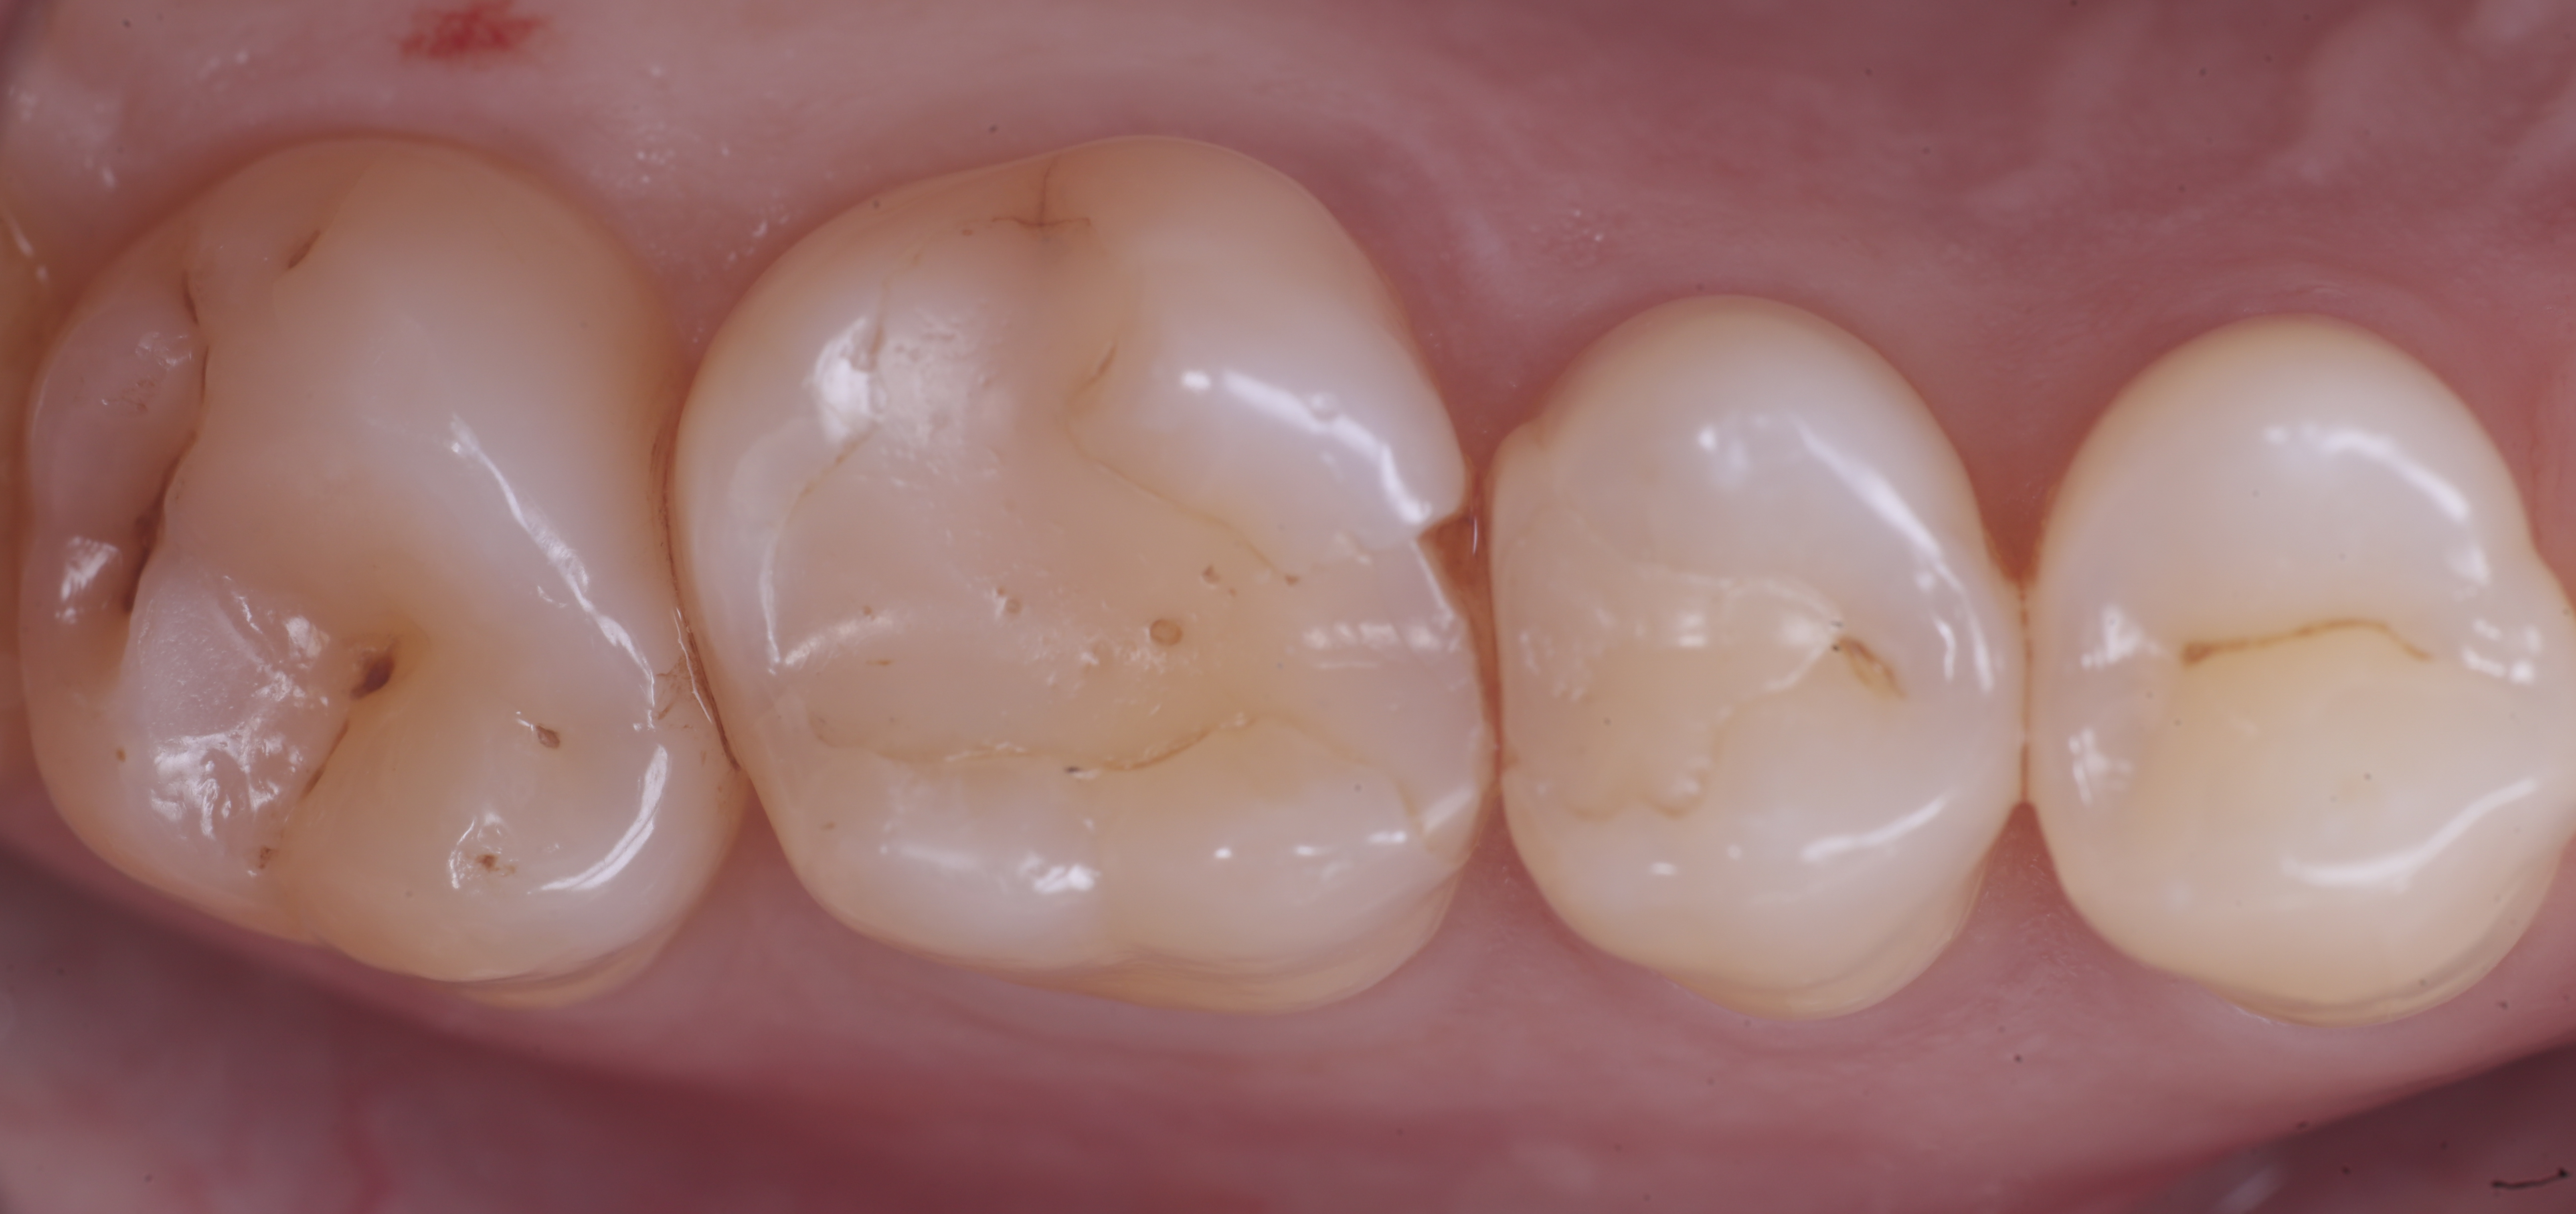

foto 8 Modellazione ed aspetto occlusale

foto 9 Modellazione ed aspetto vestibolare

foto 10 Modellazione ed aspetto palatino

foto 11 Restauri ultimati sotto controllo occlusale